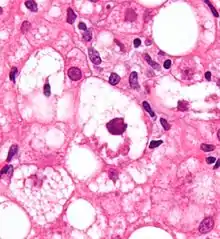

أجسام مالوري -تحت المجهر- في مركز الصورة، وتبدو بلون وردي داكن.

أجسام مالوري عالية اليوزينية (Eosinophilic) ولذلك تظهر وردية اللون بصبغة الهيماتوكسلين والإيوسين.